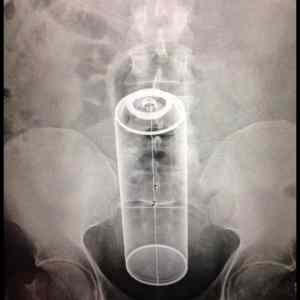

Obrázek - Candle in the wind -      06.07.2013

No však, teď už jen tam přicpat tu svíčku a ssssssssssss!

ake candle.. sak je to sprej.